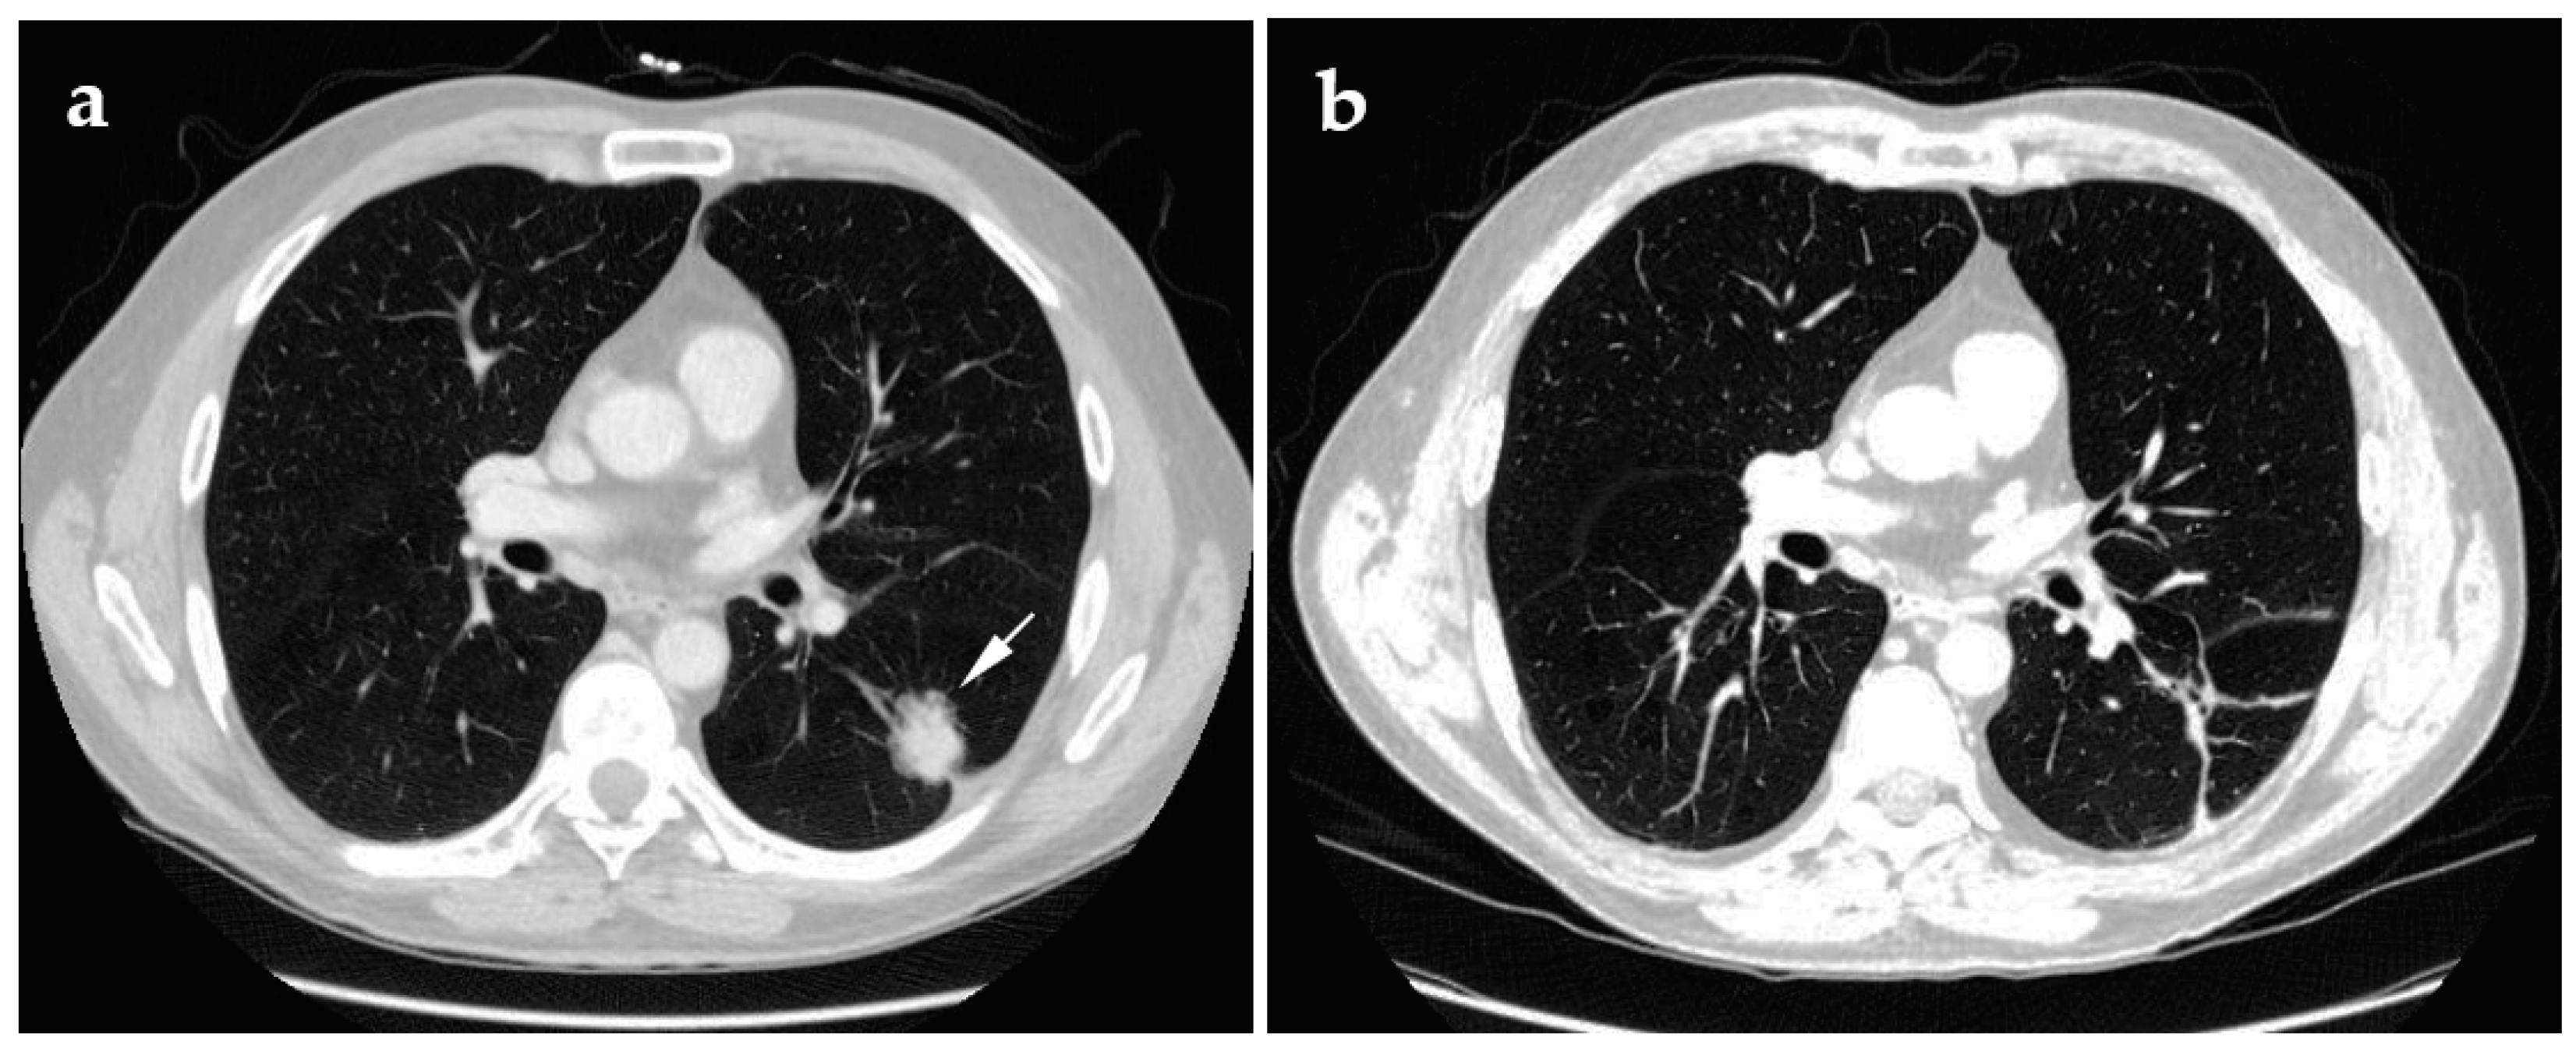

4.2. Radiofrequency Ablation